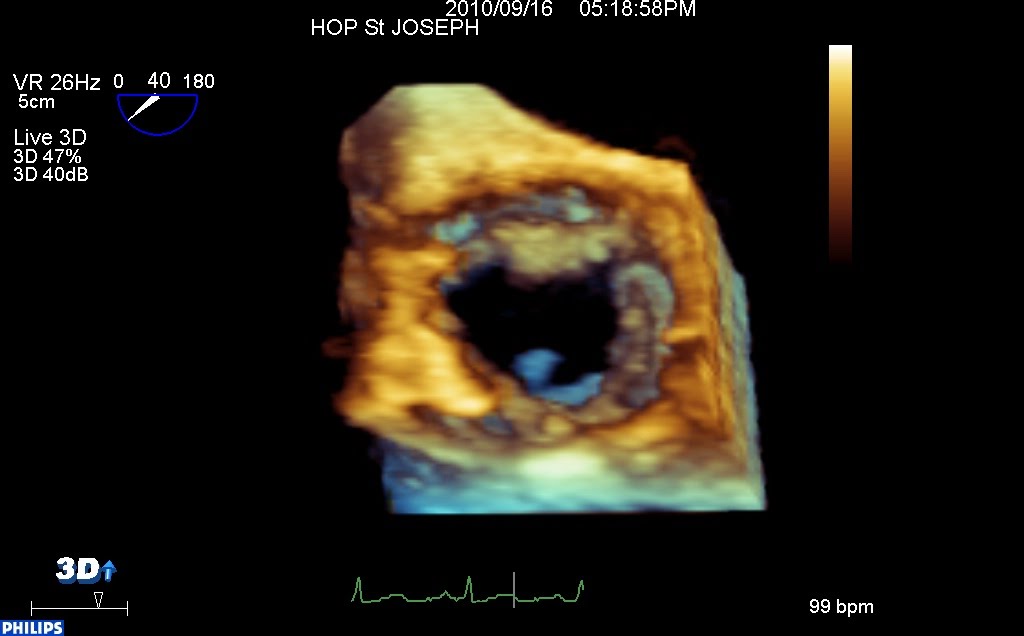

En ETO 3d, versant aortique, les dégâts valvulaires sont au premier plan, et en arrière plan, la masse mobile qui vient dire bonjour…

vue aortique 3d from fish Nip echocardiographie on Vimeo.